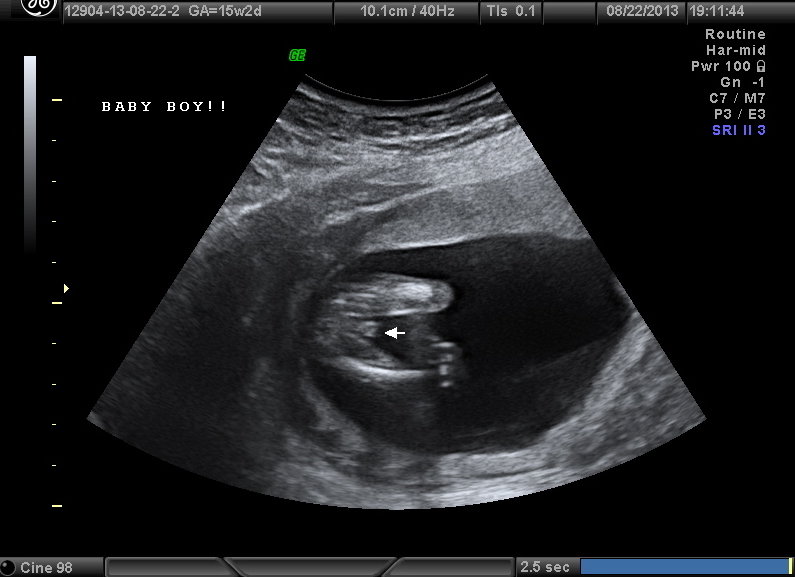

Confirmed last night, you were all right!! Here's my little BOY!!Attachment 13372

Yay!!! Congrats on the sweet baby boy!!!

Thank you, we're VERY excited!!